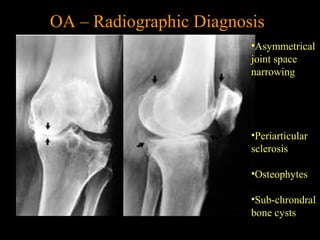

OA – Radiographic Diagnosis

•Asymmetrical

joint space

narrowing

•Periarticular

sclerosis

•Osteophytes

•Sub-chrondral

bone cysts